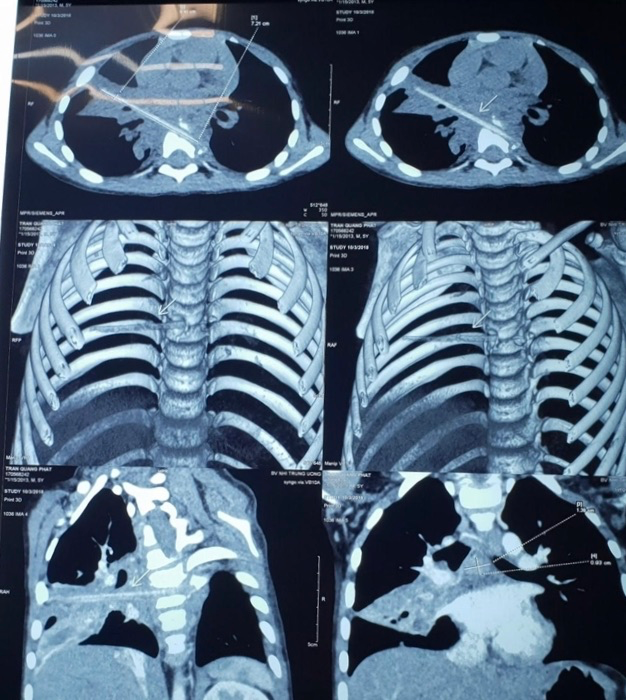

Hình ảnh que nứa dài 9cm trên phim chụp

Hình ảnh chụp vi tính cắt lớp sau đó cho thấy bệnh nhi có một dị vật dài nhọn kích thước 72x4mm tại vị trí nhu mô thùy phổi ở thùy giữa phổi phải. Dị vật này đi từ trước ra sau, xuyên qua khe giữa 2 thân đốt sống 6, 7 và làm vỡ thân đốt sống. Khi nằm lại trong cơ thể, dị vật gây phản ứng thâm nhiễm viêm trung thất sau quanh đốt sống 6,7. Đây cũng chính là nguyên nhân khiến cháu M phải vào viện vì viêm phổi trong suốt 9 tháng.